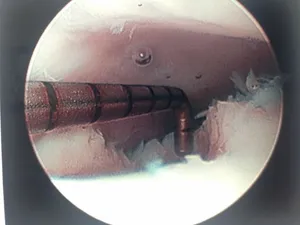

Action shot of microfracture of talus OCD.

Bleeding of OCD after microfracture.